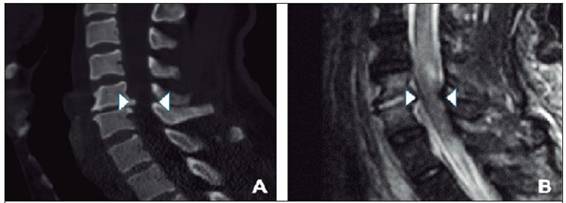

En vista de estos hallazgos, al paciente se le realizan una tomografía que evidencia un osteofíto proyectado hacia canal medular y una resonancia magnética de columna que muestra una espondilodiscitis a nivel de C5 - C6, con compromiso medular y vertebral (Figura 2). El paciente es intervenido de urgencia (fijación cervical anterior), y el material quirúrgico enviado muestra al frotis abundantes leucocitos y cocos gram positivos. El cultivo es positivo por Staphylococcus aureus meticilino-sensible con resistencia inducible a clindamicina negativa.